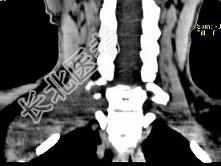

- 单项选择题女,47岁, 下颈部触及一包块约五年余,CT如图所示, 最可能诊断为  (    )

- A、滑膜肉瘤

- B、血管瘤

- C、神经鞘瘤

- D、副神经节瘤

- E、巨淋巴结增生症